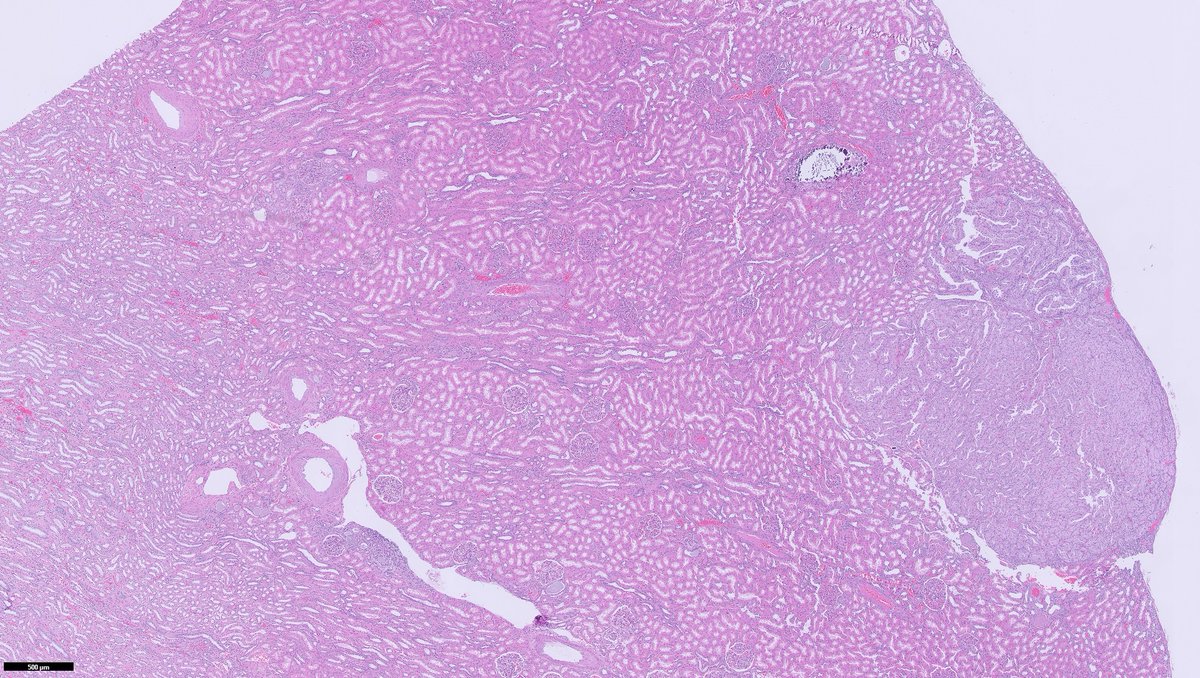

🔬YAP1::KMT2A‑rearranged sarcoma (with emphasis on diagnostic pitfalls)🔬

Rare fibroblastic sarcoma recently defined by YAP1::KMT2A fusion and a unique methylation profile, often mimicking sclerosing epithelioid fibrosarcoma (SEF), low‑grade fibromyxoid sarcoma (LGFMS), or even benign fibroblastic lesions.

Soft tissue sarcoma characterized by YAP1–KMT2A/KMT2A–YAP1 fusions, SEF‑like/LGFMS‑like morphology, and an epigenetic cluster distinct from classic MUC4‑positive SEF and LGFMS.

Histopathology 🔬

Architecture: grossly nodular tumors, but with infiltrative borders and “honeycomb” spread through subcutaneous fat and skeletal muscle.

Cytology: ovoid/epithelioid cells in cords, nests or solid sheets within dense collagenous stroma; mitotic activity usually low in hypocellular areas, higher in more solid/anaplastic foci.

Special patterns: perineurioma‑like areas (bland spindle cells in whorled/loose‑storiform pattern), fibroma‑like zones (very dense collagen with sparse cells), and foci of small round or rhabdoid cells in recurrences/metastases.

Additional findings: thin‑walled vessels (sometimes hemangiopericytoma‑like); typical absence of alternating fibromyxoid zones and classic collagen rosettes of LGFMS.